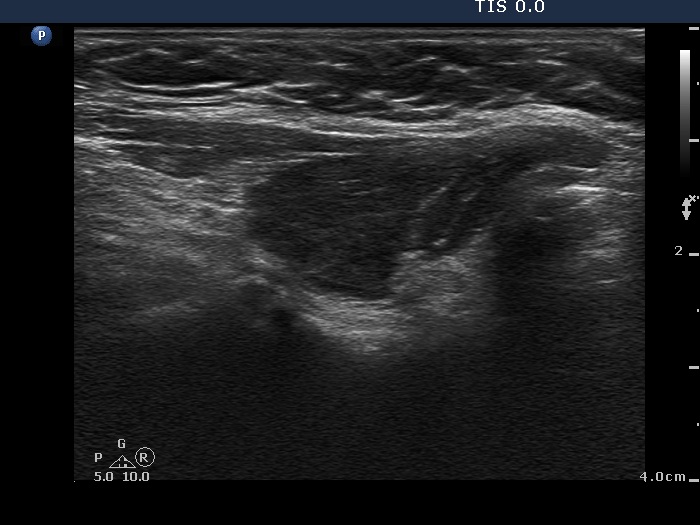

Ultrasonography. Both lobes were composed of a central hypoechogenic part surrounded with an echonormal rim. Although this pattern resembles that of a large hypoechogenic nodule occupying almost the entire lobe, this is one of the characteristic presentations of Hashimoto's thyroiditis. In contrast with a nodule, the borders between the central hypoechogenic area and the surrounding echonormal rim are irregular.